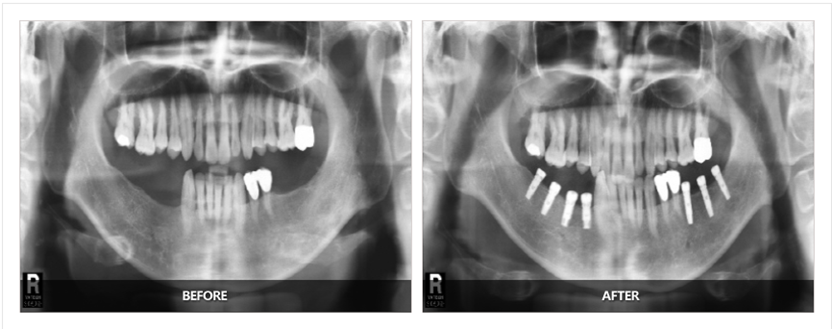

拓展知識:種植牙基臺應該漏出多少